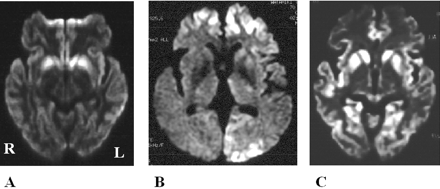

酒后驾驶是在26日检查库贾氏症患者发病后3到25周平均持续时间为10.7周。24库贾氏症患者表现出高强度脑损伤的驾车考试。两个观察者,醉酒驾车的库贾氏症诊断的敏感性为92.3%。interobserver协议率为100%。3例(12.5%)显示只在尾状头和硬膜损伤,10例(41.7%)患者显示线性损伤只有在大脑皮层,和11例(45.8%)患者显示病变基底神经节和大脑皮层(图1)。其中,只有三个病人(12.5%)显示,丘脑病变。没有病人显示高强度在小脑病变。高强度损伤在驾车之前出现脑萎缩。病变包括纹状体初并不总是对称的但是后来对称(图2),尽管对称的纹状体病变是众所周知的在库贾氏症。11在某些情况下,高强度损伤与连续驾车并不总是进展的疾病,而有时信号强度降低了疾病进展的一些病变。在某些情况下,皮质高信号强度不同,解剖分布(图3)。在终端阶段与深刻的脑萎缩,高强度损伤变得不清楚。T2I DWI-examined 26日在23日检查病人,但T2I扫描被排除在外,因为低质量由于运动构件。一位观察家认为11 22患者阳性(50.0%),而另一个观察者认为8阳性(36.4%)。interobserver协议率为68.2%,低于酒后驾车(p< 0.005)。在这两个观察者,醉酒驾车是比T2I更敏感(p一个观察者,< 0.005p另一个观察者p < 0.0005)。天赋是17 26患者的检查。一位观察家认为10 17例阳性(58.8%),和另一个观察者认为7是积极的(41.2%)。interobserver协议率为82.4%,也低于酒后驾车(p< 0.05)。醉酒驾车是比天赋更敏感(p一个观察者,< 0.01p另一个观察者p < 0.0005)。我们在图4一个例子中,只有醉酒驾车可以检测高强度异常病变。

图2。按时间顺序的改变的纹状体和皮质病变。零星的克雅氏病(CJD)显示基底神经节的进展信号变化不对称对称(B) (A)。(A)和(B)之间的间隔是2个月。的家族与V180I突变库贾氏症显示大脑皮层的进展和尾状核头信号变化不对称(C)对称(D)。(C)和(D)之间的间隔是4个月。